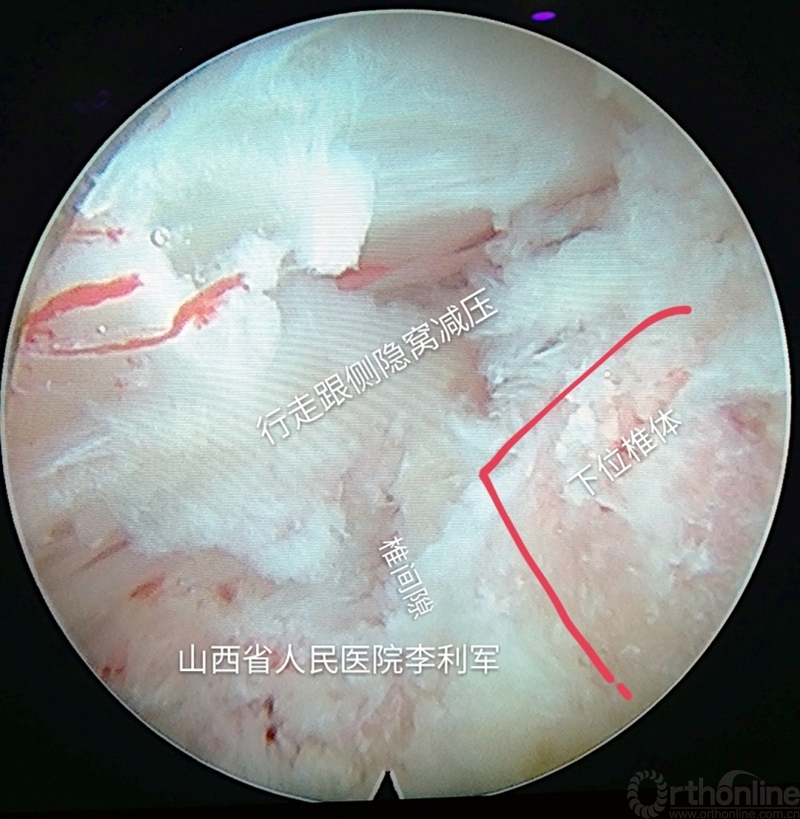

第七步:逐步调整和旋转通道,移向行走根侧隐窝区,做此处减压,根据具体情况可以再重复上述成型的过程去除阻挡的关节突,达到这个部位的减压。如图15-16

图15 逐步调整通道做行走根侧隐窝区减压

图16 逐步调整通道做行走根侧隐窝区减压